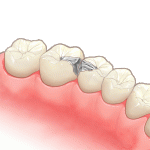

③インレーを入れます

-

その後、実際にお食事をして、噛み合わせが問題ないか確認してください。

必要に応じて噛み合わせの調整を行います。また虫歯が大きい場合、虫歯を取った時の刺激で数日シミたり、痛むことがありますが、基本的には歯の神経が馴染んでくると症状はなくなりますのでご安心ください。しかし、あまりにも症状が消えない場合は神経の処置が必要になります。